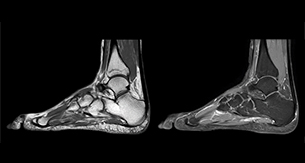

“In peripheral joints, mDIXON TSE imaging aids in diagnosing injuries in ligaments or tendons, for imaging degenerative and inflammatory pathologies such as osteoarthritis and rheumatologic disorders and for oncological exploration.”

“For tendon and ligament assessment around knee, ankle, hip and elbow, mDIXON TSE contributes to diagnostic confidence thanks to having images both with and without fat suppression – and without time penalty. This is possible because 2-point mDIXON is faster than the common 3-point Dixon method. It can also increase efficiency as it helps avoid having to add scans during the exam.”

“In peripheral joints, we get good image quality in difficult areas with mDIXON TSE.

Fat suppressed images appear homogeneous over the entire image, even with large coverage at 3.0T – for instance in scapular or hip girdles – or in the bearing areas or around metal prostheses, where fat suppression is often deficient with STIR or spectral fat suppression, causing diagnostic difficulties. If a diagnostic image is right the first time, we don’t need to repeat or add a sequence.”

“mDIXON TSE sequences allow simultaneous characterization of morphological changes from the in-phase T2-weighted images and visualization of edematous changes, thanks to the water T2-weighted images from the same acquisition. Anatomical and morphological considerations could be a partial or complete ligament tear, a bony avulsion or hematoma.”

“For soft tissue assessment mDIXON brings similar benefits. For example in one T2-weighted mDIXON TSE acquisition, having the multiple contrasts helps us assess abnormalities in peripheral nerves fascicles, which may be due to anatomical or inflammatory changes..”